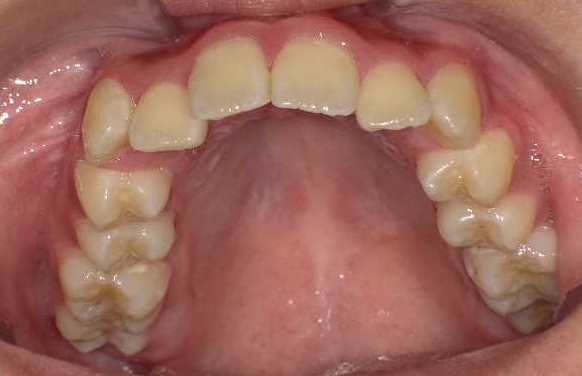

症例1-①

症例1-①の写真をご覧ください。著しく顎が小さく左の上下犬歯の萌出スペースがほとんどありません。ここで、歯ならびの相談に行くとおそらく将来、永久歯を抜くことになると言われることでしょう